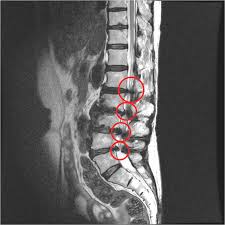

- MRI: 신경압박 정도, 협착 위치·범위 정확하게 파악

🩻 진단 방법